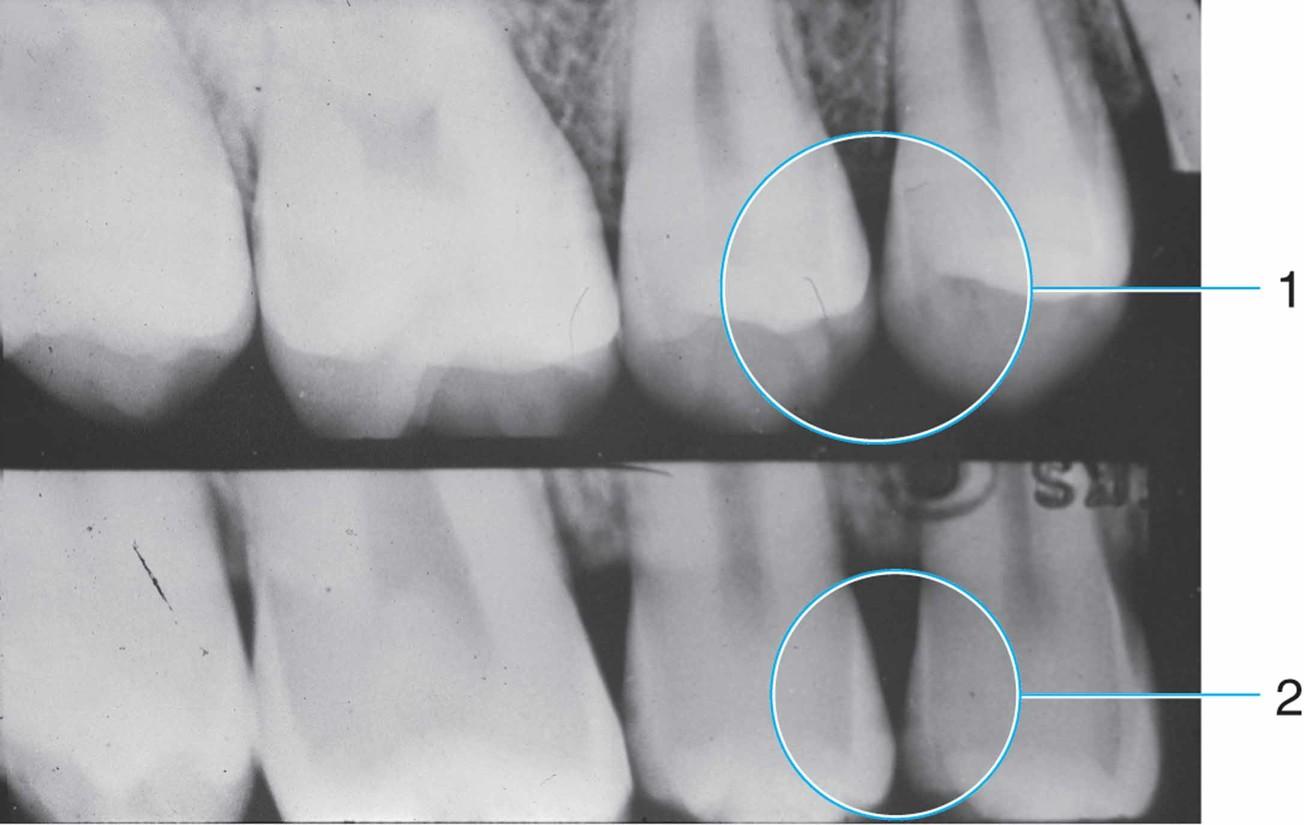

Скрытые повреждения эмали можно выявить при помощи трансиллюминации зубного ряда. Достаточно часто для выявления очагов заболевания применяют рентгенографические методы диагностики.

Результат рентгеноскопического обследования зубов пораженных первичным, поверхностным кариесом.

Поверхностный кариес дифференцируется с эрозией эмали, флюорозом, клиновидным дефектом, а также с более глубокими формами кариозного поражения — глубокой и средней стадией заболевания.